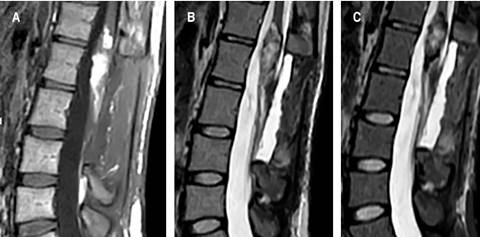

Female patient, 26 years old, with a history of pain in the right pelvic member of six years of evolution, with progressive claudication, repeated urinary tract infections, emergency urinary incontinence, admission to the emergency service, with an incidentally finding an intramedullary cyst from the vertebral body T12 to L3, with heterogeneous enhancement with intravenous contrast (Figure 1). Surgical resection was performed with neuro monitoring and posterior approach, laminectomy of L1 and L2, with the finding of an intradural extramedullary encapsulated macroscopically with pearled appearance, dismissable consistency, and easily resectable. Satisfactory macroscopic resection was performed, leaving a small remnant attached to the medullar cone (Figure 2). The histopathological report of the lesion was abundant keratin, compatible with a dermoid cyst (Figure 3). The patient left the hospital two days after the procedure, without sensory or motor deficit in the lower limbs, in follow-up at 2 weeks showed improvement in urinary incontinence. Postoperative magnetic resonance imaging was performed where a small remnant is observed at the level of the spinal cord cone (Figure 4).

Figure 4: Postoperative lumbar MRI sagittal view. A) T1, B) T2, C) STIR.